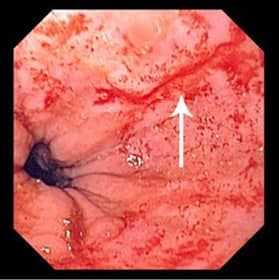

- Эзофагогастроскопия. Введение гибкого эндоскопа через ротовую полость позволяет оценить состояние эпителиальной оболочки верхних отделов ЖКТ и обнаружить линейные разрывы, которые обычно локализованы в области перехода пищевода в желудок. С помощью визуального осмотра удается установить глубину поражения стенки пищевода или желудка.

• Эзофагогастроскопия. Введение гибкого эндоскопа через полость рта позволяет оценить состояние эпителиальной мембраны верхних отделов желудочно-кишечного тракта и выявить линейные разрывы, которые обычно расположены в зоне перехода пищевода в желудок. При визуальном осмотре можно определить глубину поражения стенки пищевода или желудка.

Окончательный диагноз Синдром Мэллори-Вейса ставится во время проведения ЭГДС. Как правило кровотечение останавливается самостоятельно за 24—48 часов. Иногда требуется эндоскопическое лечение. Открытое вмешательство выполняется при тяжелой степени кровопотери и безуспешности эндоскопического гемостаза, выраженных анатомических поражениях кардиального жома.